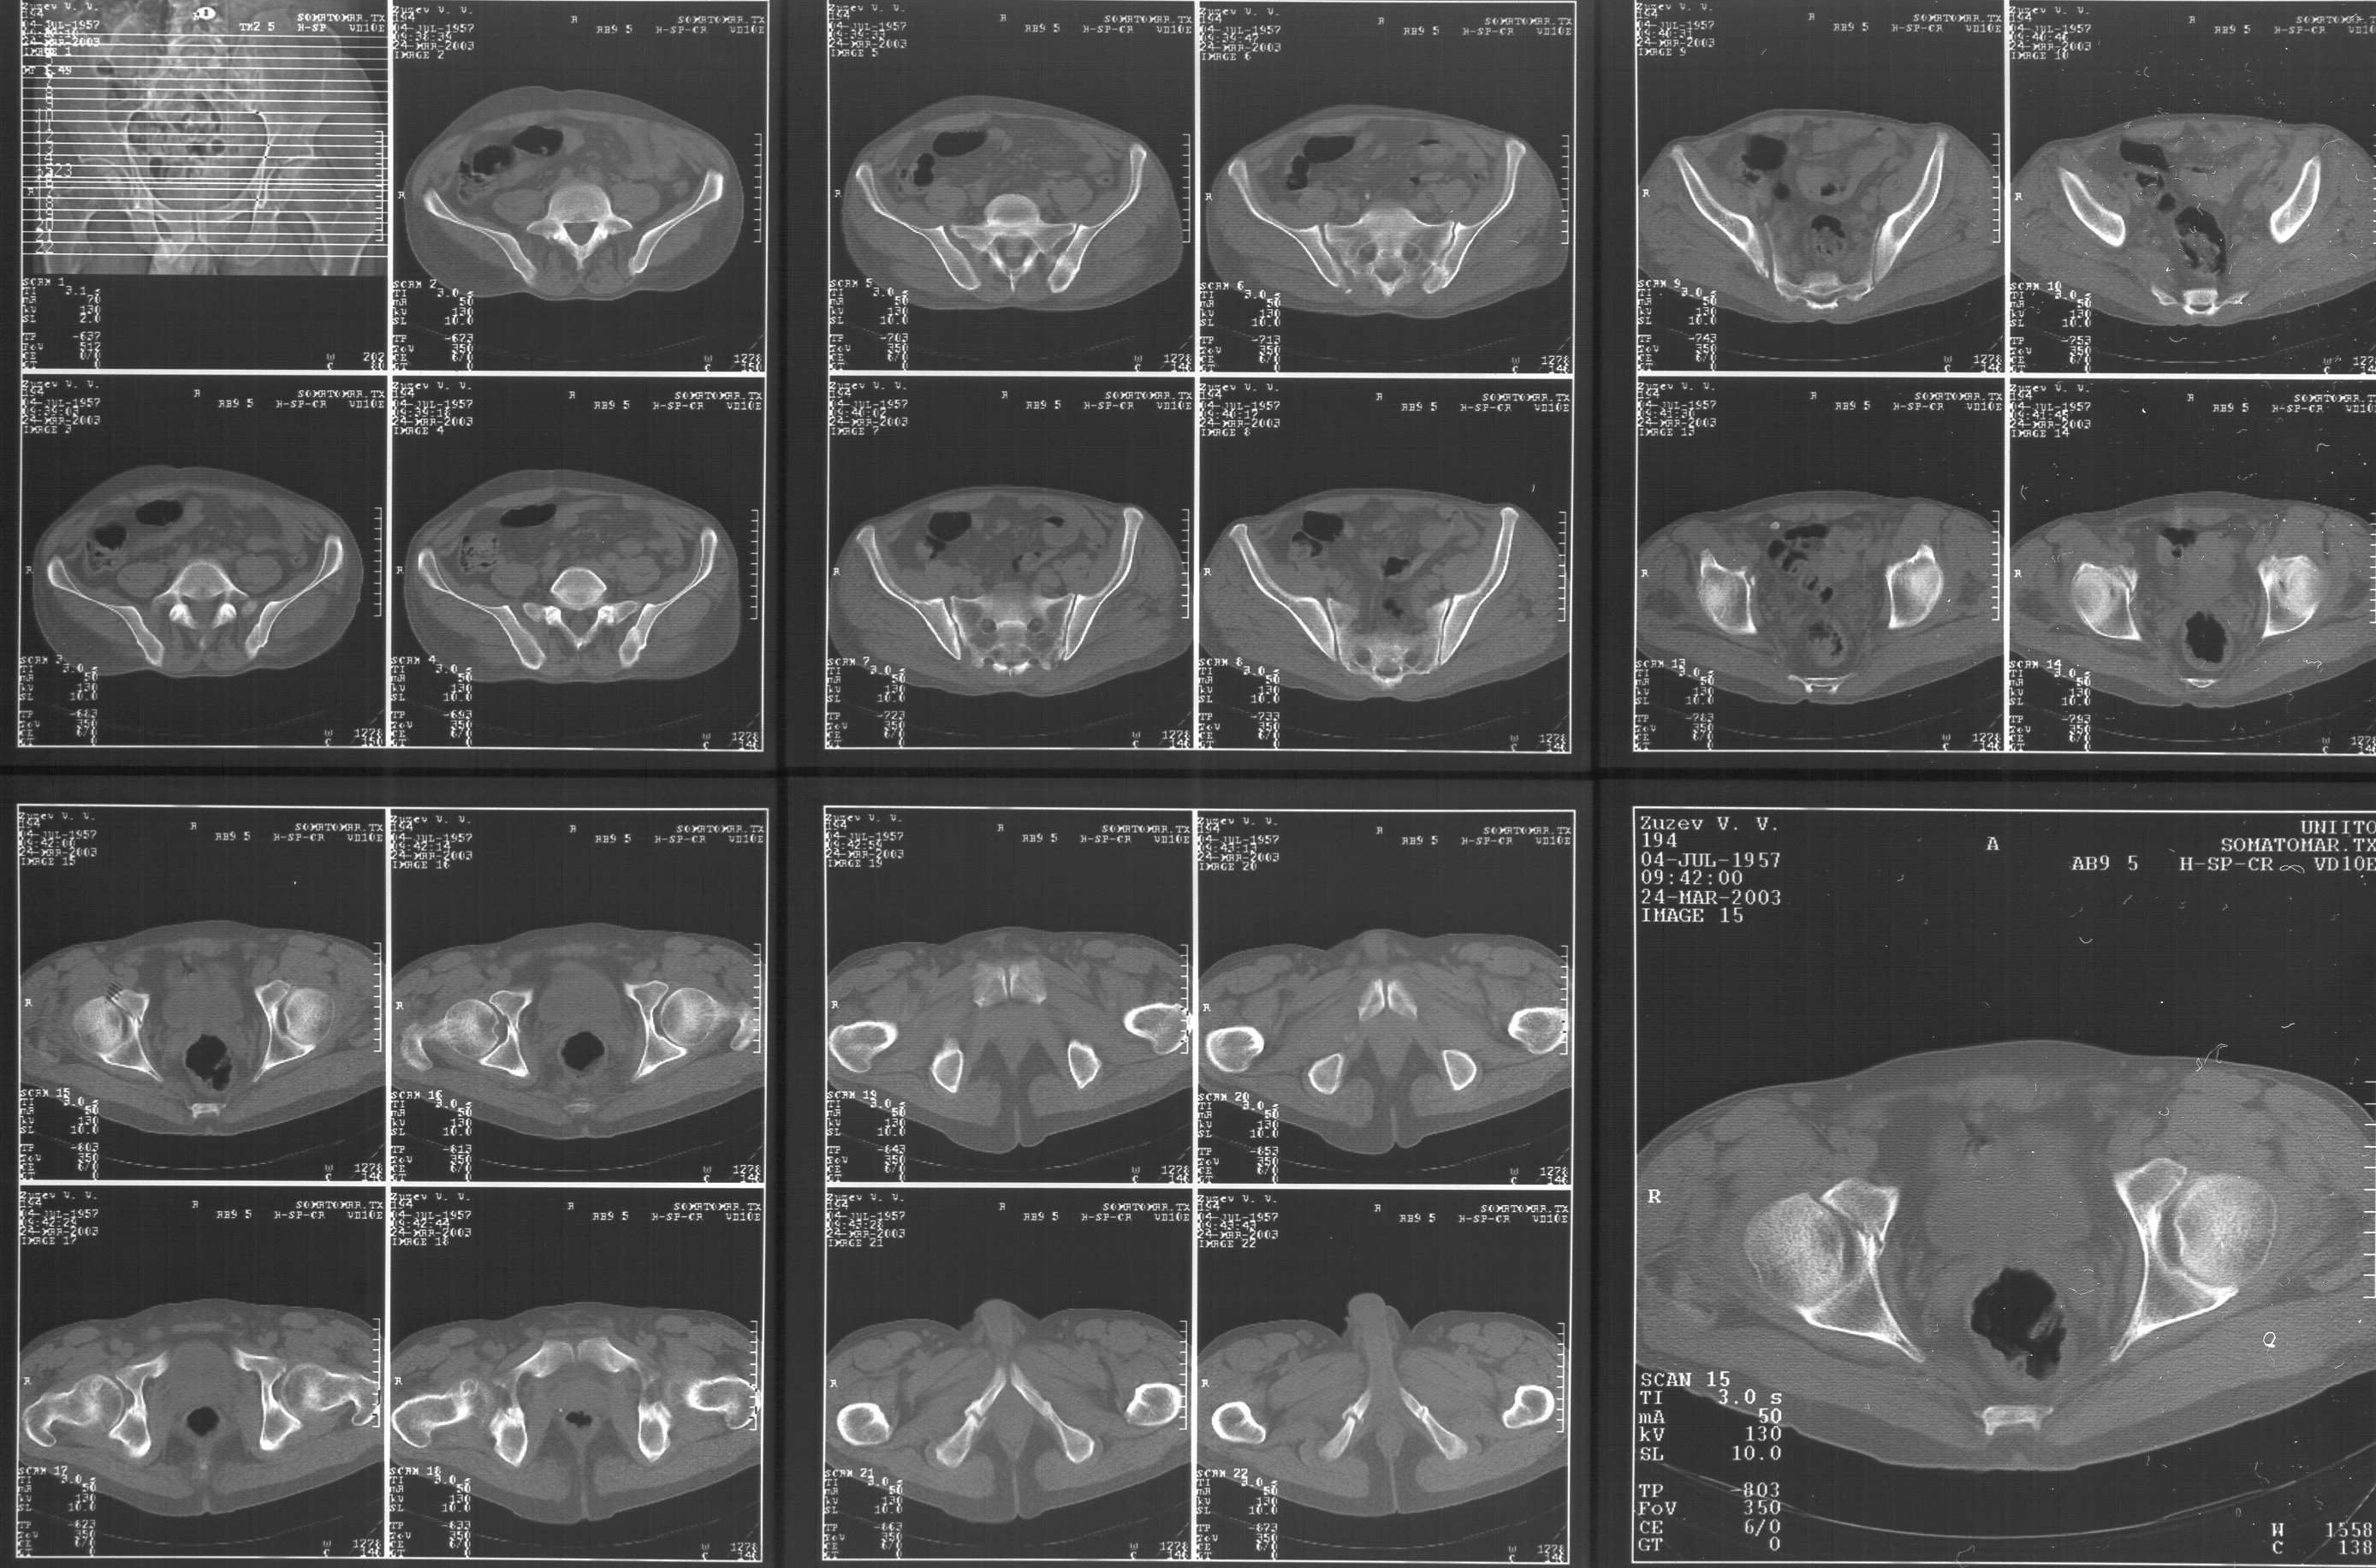

Прилагаю свежую КТ таза.

Картинки см. ниже, левая - с экранным разрешением, вторая - полноразмерная, ~900 кб.

КТ в экранном разрешении

Полноразмрная картинка, около 900 кб

Как Вы сами видели на томограммах, грубых деструктивных явлений крестцово-подвздошного сочленения не определяется( маркировка правая -левая сторона не видна), определяется сравнительно незначительное расширение суставной щели с одной стороны и не более того.

Виноват, первый раз не обратил внимания на возможность полноформатного просмотра томограмм. В этой связи -дополнения к своему первому комментарию: сросшийся перелом вертлужной впадины справа, L5-S1 спондилоартроз, расширение суставной щели крестцово-подвдзошного сочленения справа может компрометировать его стабильность и вызывать локальные боли, но вряд ли это может давать двусторонние проявления в нижних конечностях. Все-таки миелограмма или ЯМР желательно иметь, чтобы определиться в тактике.